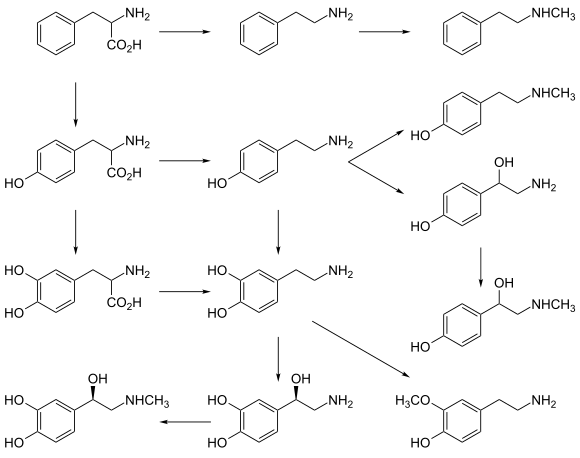

Dopamine is synthesized in a restricted set of cell types, mainly neurons and cells in the medulla of the adrenal glands.[23] The primary and minor metabolic pathways respectively are:

- Primary: L-Phenylalanine → L-Tyrosine → L-DOPA → Dopamine[20][21]

- Minor: L-Phenylalanine → L-Tyrosine → p-Tyramine → Dopamine[20][21][22]

- Minor: L-Phenylalanine → m-Tyrosine → m-Tyramine → Dopamine[22][24][25]

The direct precursor of dopamine, L-DOPA, can be synthesized indirectly from the essential amino acid phenylalanine or directly from the non-essential amino acid tyrosine.[26] These amino acids are found in nearly every protein and so are readily available in food, with tyrosine being the most common. Although dopamine is also found in many types of food, it is incapable of crossing the blood–brain barrier that surrounds and protects the brain.[27] It must therefore be synthesized inside the brain to perform its neuronal activity.[27]

L-Phenylalanine is converted into L-tyrosine by the enzyme phenylalanine hydroxylase, with molecular oxygen (O2) and tetrahydrobiopterin as cofactors. L-Tyrosine is converted into L-DOPA by the enzyme tyrosine hydroxylase, with tetrahydrobiopterin, O2, and iron (Fe2+) as cofactors.[26] L-DOPA is converted into dopamine by the enzyme aromatic L-amino acid decarboxylase (also known as DOPA decarboxylase), with pyridoxal phosphate as the cofactor.[26]

Dopamine itself is used as precursor in the synthesis of the neurotransmitters norepinephrine and epinephrine.[26] Dopamine is converted into norepinephrine by the enzyme dopamine β-hydroxylase, with O2 and L-ascorbic acid as cofactors.[26] Norepinephrine is converted into epinephrine by the enzyme phenylethanolamine N-methyltransferase with S-adenosyl-L-methionine as the cofactor.[26]